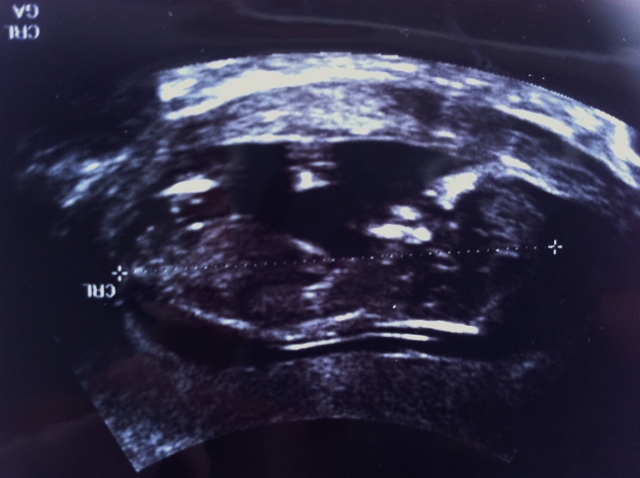

This is my US at 12 weeks + 3 days. The baby was upside down, so I had to turn the picture. I'm not sure, but I see something sticking out (very far up towards the face) where te NUB should be. Is this the NUB? Any ideas from the skull?